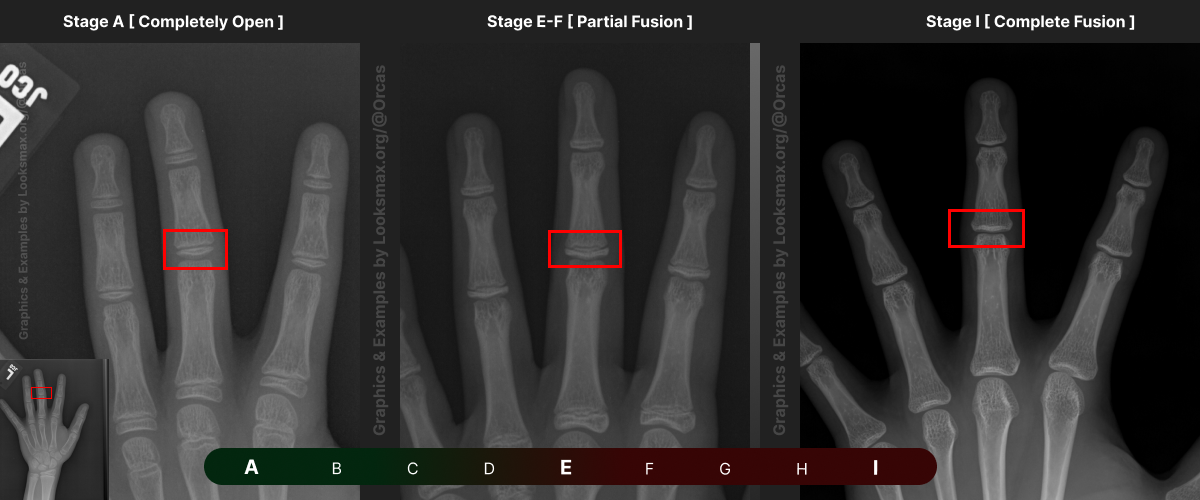

Bonetype: 3rd Metacarpal (middle finger)

Check & use the chart below to figure out where you are. Then write your result on a piece of paper or a text file.

Bonetype: 3rd Middle Phalanx

I added references for stages A (Completely unfused), E-F (Partial fusion, basically late stages of puberty), and I (Complete Fusion)

You will have to eyeball this now using your own xrays, I’ve given three examples and some wiggle-room for letters using a reference bar (green-red) below the image, write down your estimated guesses in a text file until you finish all 13 bones.